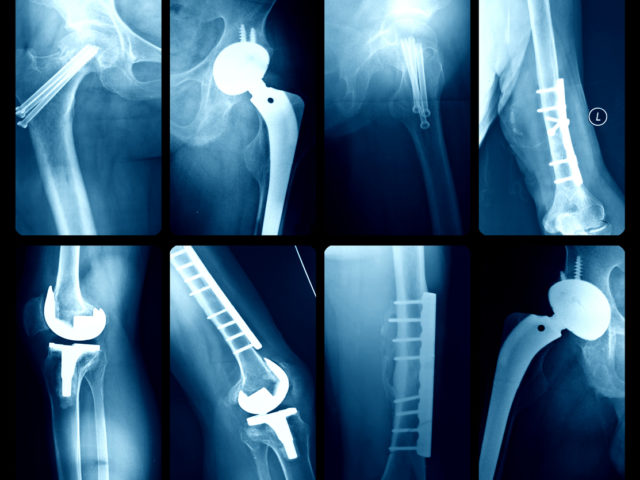

Facts on Joint Replacement Surgery

The body is an amazing machine, but it can break down due to injury and overuse. Thanks to advancements in medical materials and surgical techniques, joint replacement surgeries are now being done in greater numbers than ever before. The most common full joint replacement surgeries are done on the knee, hip, and shoulder. And with…